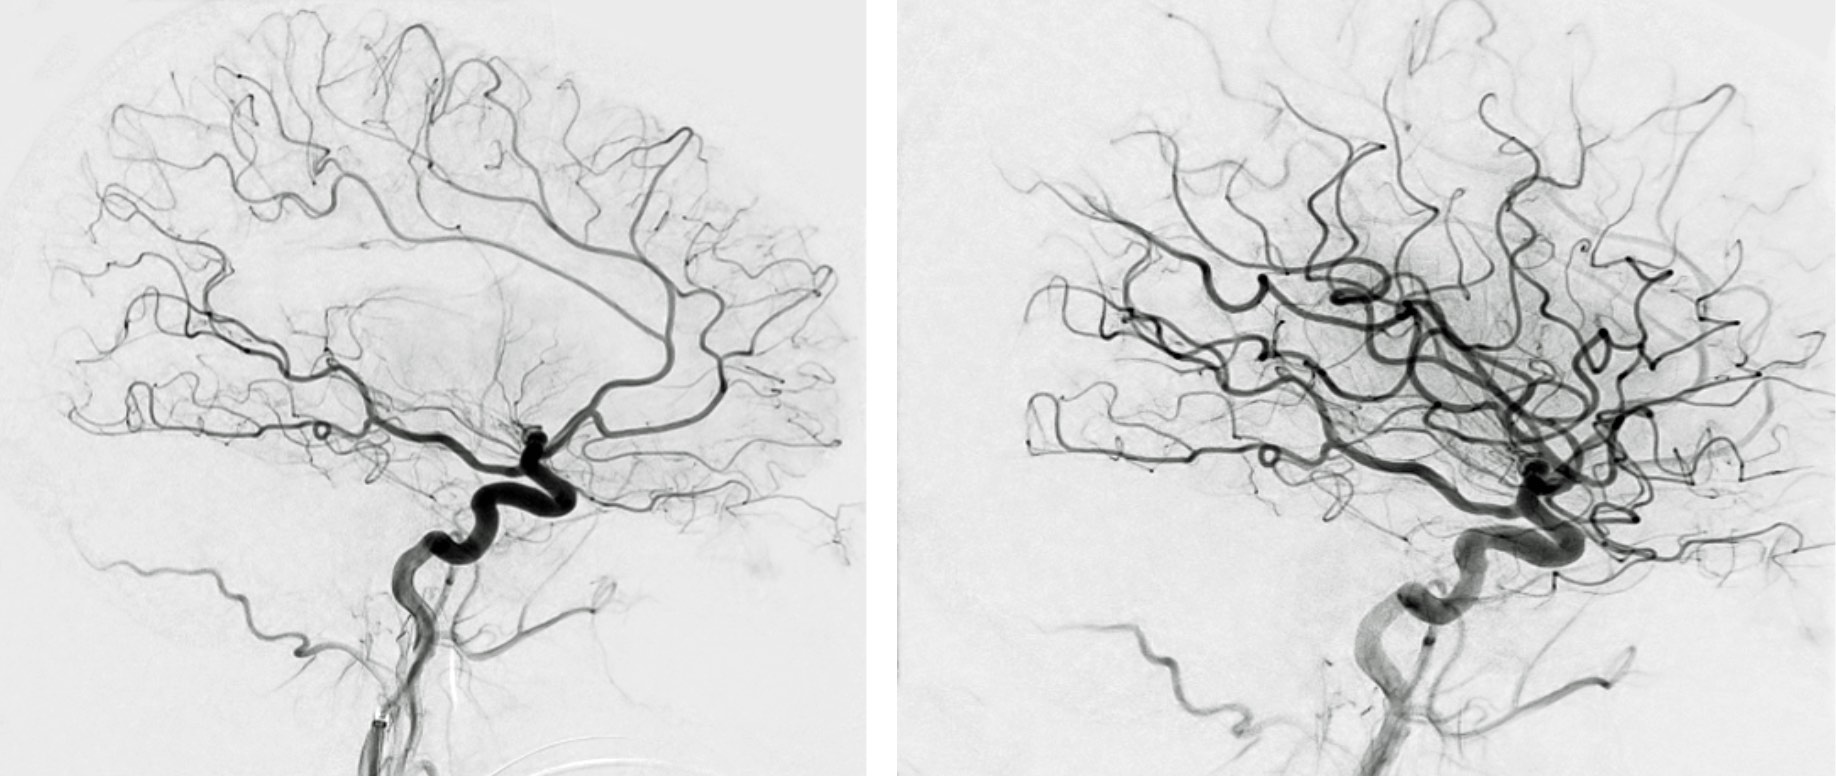

These images show blood vessels in the brain (black squiggles). At left, a blood clot is keeping blood from flowing to a large area at the center of the patient’s brain. At right, mechanical thrombectomy has restored blood flow to the areas affected by the stroke.